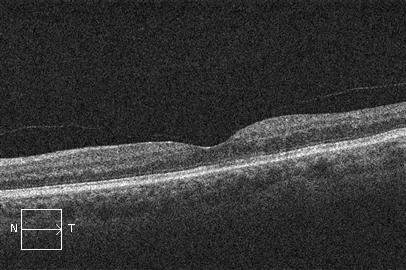

La OCT (tomografía de coherencia óptica) permite valorar la presencia y grado de inflamación en la zona central de la retina (edema macular).

OCT. Edema macular por oclusión venosa retiniana antes del tratamiento